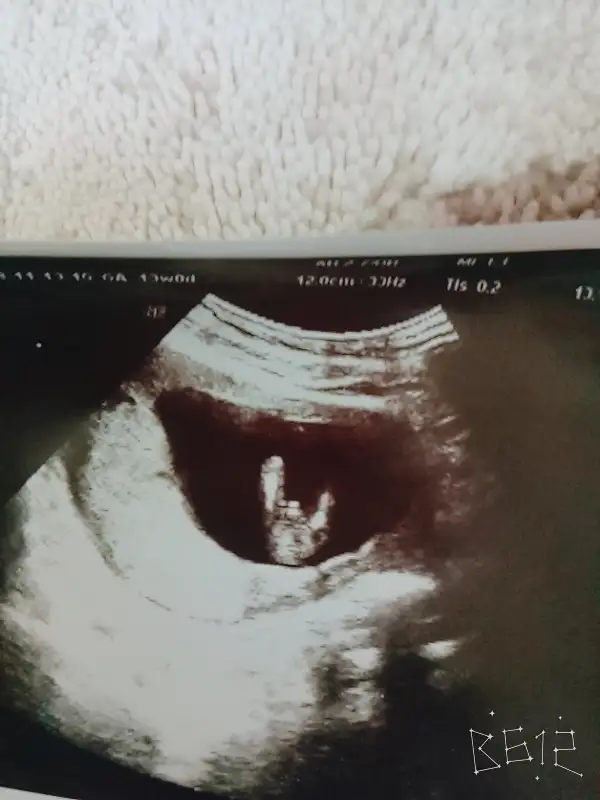

Eki Görüntüle 2205522 bu da ultrasonumuz masallah kuzuma.

Sorma baya acmis sagolsunAy maşallah yavruna canım ne de güzel poz vermişgayet net pipi